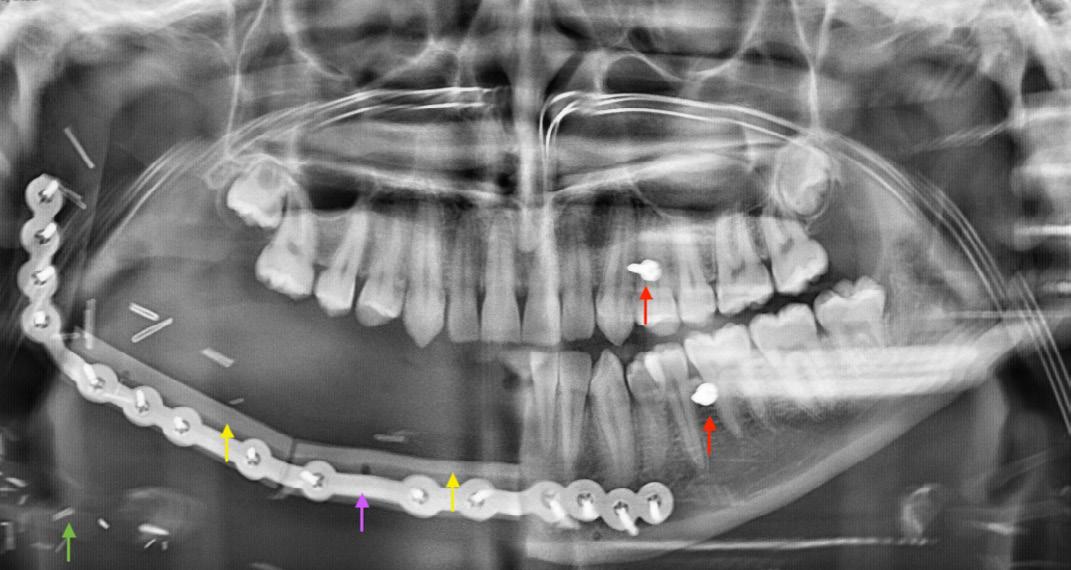

Primary inferior alveolar nerve protection: a CAD/CAM approach

Betar N, Badri D, McCombe A and Finn B